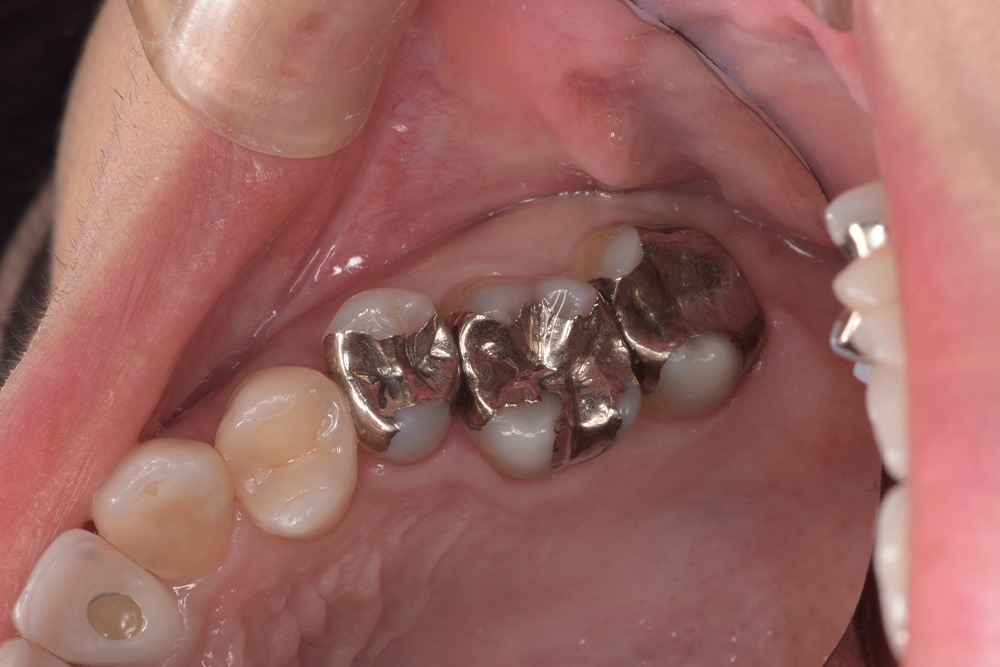

| 治療経過 | 銀歯の隙間にフロスが引っかかるとのことで治療介入となった。 銀歯の下は全て虫歯になっており、今後虫歯のリスクを軽減させることを目的として、歯への接着力、清掃性に優れたセラミックを用いた修復方法を選択した。 |